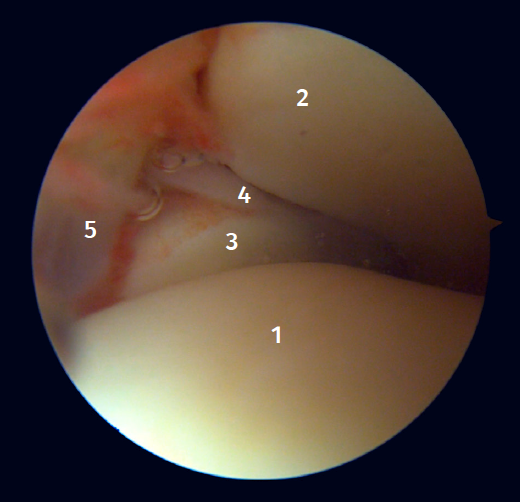

Visión artroscópica anterior

El 20% del LTPA es intraarticular(7). Cuando realizamos un acceso anteromedial del tobillo dirigiendo el artroscopio hacia lateral podemos ver las fibras distales del LTPA con su disposición oblicua y su continuación con el ligamento peroneo-astragalino anterior (Figura 2). Si avanzamos dentro de la articulación tibioastragalina, veremos la articulación tibioperonea distal con el receso sindesmal ocupado de tejido sinovial (Figura 3).

Figura 2. Visión artroscópica anterolateral del tobillo derecho. 1: cúpula astragalina; 2: cara anterior de la tibia; 3: peroné; 4: fibras distales del ligamento tibioperoneo anterior; 5: ligamento peroneo-astragalino anterior.